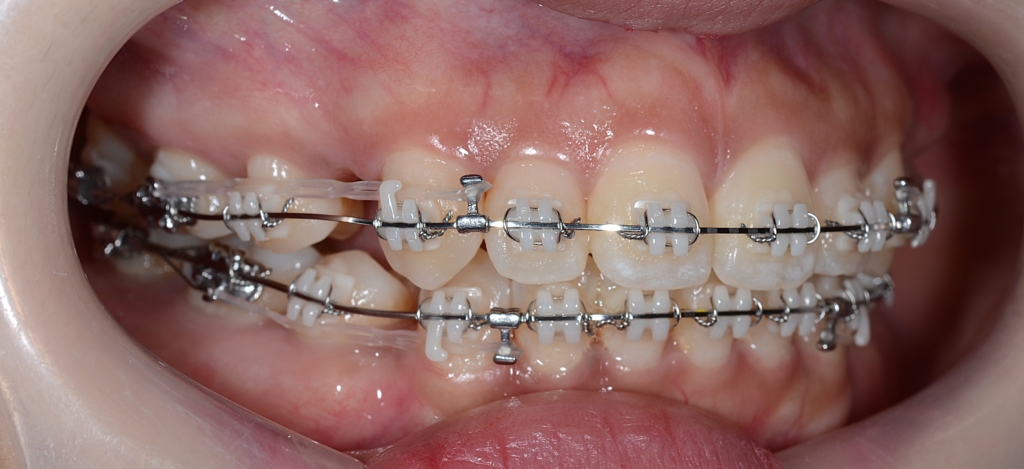

順調にステップが進み、前歯を最大限に引っ込めるステップに入りました。

【上の歯列の更なる後方への移動を図る】

隙間分はしっかり引っ込めたのですが、元の噛み合わせが上顎前突傾向でしたので、出っ歯が残ってしまいました。 そこで、より引っ込んだ下の歯列に上の歯列を引っ込めて合わせるという次のステップに進めることにしました。

あらためて、上顎にアンカースクリューを植立しました。

アンカースクリューを用いて矯正力を加えることで、上顎歯列全体を後方へ移動させて、口元の見た目の更なる改善を図ります。

同じことをしている方の写真をイメージ写真としてあげています。